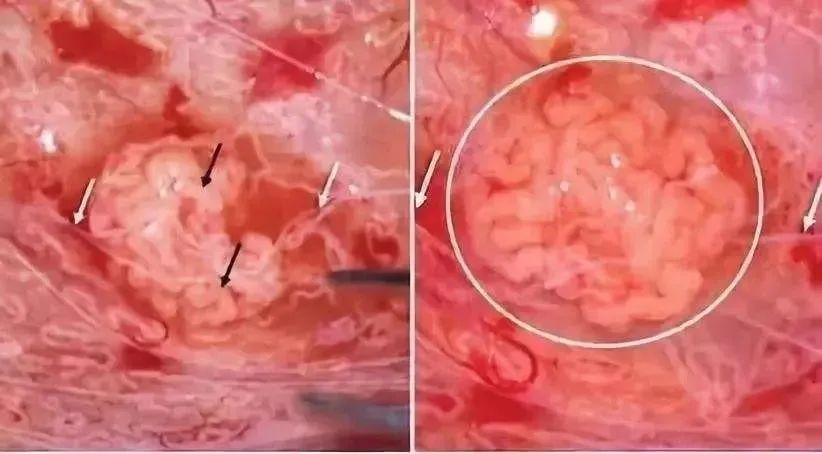

对于宝宝来讲,子宫是一个“单人间”,如果子宫里面胚胎数目植入得越多,那么每个胚胎获取的营养就越少,这就可能导致胎儿宫内生长迟缓、畸形、连体婴儿等问题。